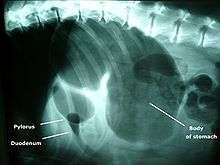

A diagnosis of gastric dilatation-volvulus is made by several factors. The breed and history will often give a significant suspicion of gastric dilatation-volvulus, and the physical exam will often reveal the telltale sign of a distended abdomen with abdominal tympany. Shock is diagnosed by the presence of pale mucous membranes with poor capillary refill, increased heart rate, and poor pulse quality. X-rays (usually taken after decompression of the stomach if the dog is unstable) will show a stomach distended with gas. The pylorus, which normally is ventral and to the right of the body of the stomach, will be cranial to the body of the stomach and left of the midline, often separated on the x-ray by soft tissue and giving the appearance of a separate gas filled pocket (double bubble sign).[17]